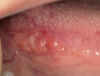

Which systemic disease manifests like this?

Crohn Disease

- Patients can also get angular cheilitis

- Above the Linear ulceration, can see a flap like structure which is the hyperplastic margin